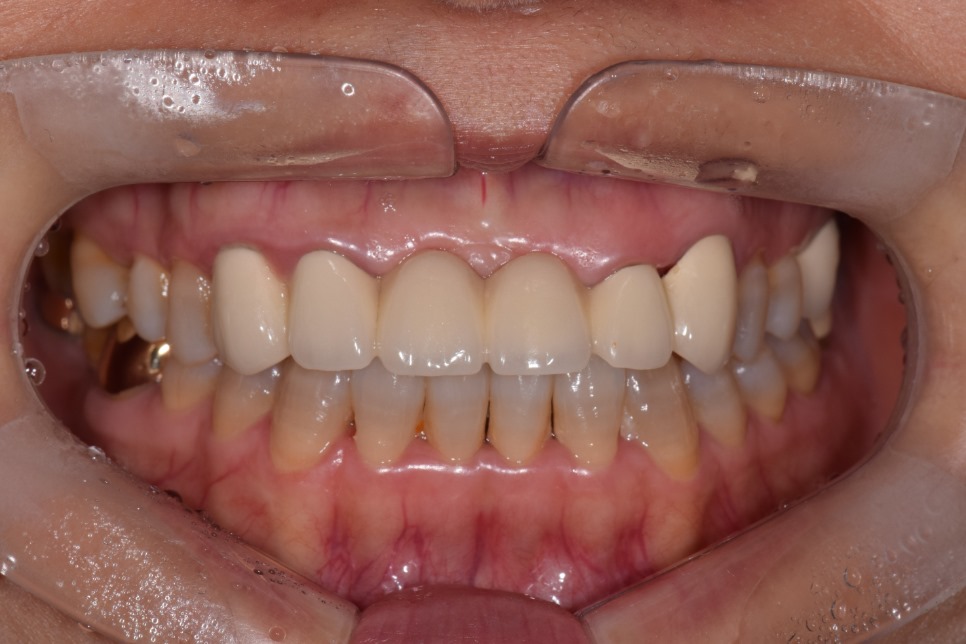

위 사진은 잇.몸.성.형 후 올세라믹 크라운 세팅하셨네요.

치아의 투명도, 크기 ,모양, 잇몸라인 꽤 괜찮아 보입니다. 환자분도 만족하셨고요.